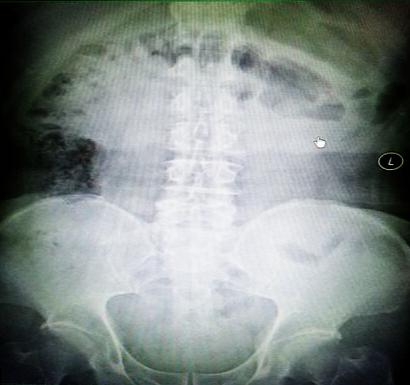

受試患者在結(jié)腸端端吻合術(shù)中,使用我司新研制產(chǎn)品達(dá)到了理想的預(yù)期效果。患者術(shù)后7天、14天X光片顯影,可降解腸道支架均能按研制設(shè)計的預(yù)期時間節(jié)點(diǎn)保持應(yīng)有強(qiáng)度,術(shù)后21天X光片顯示可降解腸道支架已完全破碎,并排出體外。在整個試驗(yàn)過程中,病患無任何不良反映,耐受良好。